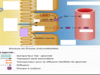

Quelles sont les deux faces du reins?

- convexe, externe

- concave, interne fait face à la colonne vertébrale (fente verticale ou hile au niveau duquel: uretère, nerfs issus du SNS*, artère et veine rénales, ainsi que vaisseaux lymphatiques)

Quelles sont les 3 zones du rein?

- externe (cortex rénal)

- intermédiaire (médullaire rénal ou médulla)

- interne (bassinet)